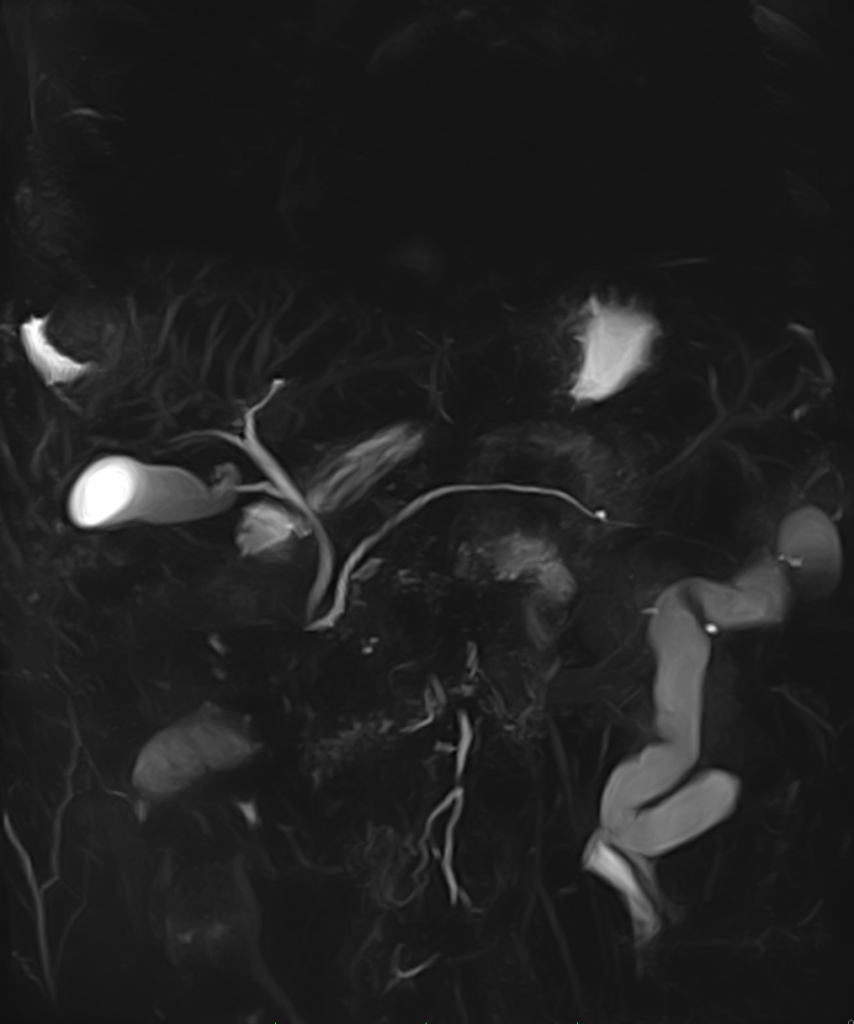

High Quality Images in high vision field

Clinical Images